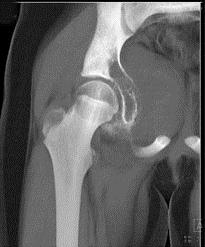

问题 男,15岁,右髋部疼痛、红肿,有压痛,皮温增高,结合图像,最可能的诊断是 ( )

选项 A、转移性神经母细胞瘤 B、骨结核 C、急性骨髓炎 D、Ewing肉瘤 E、骨肉瘤

答案 D